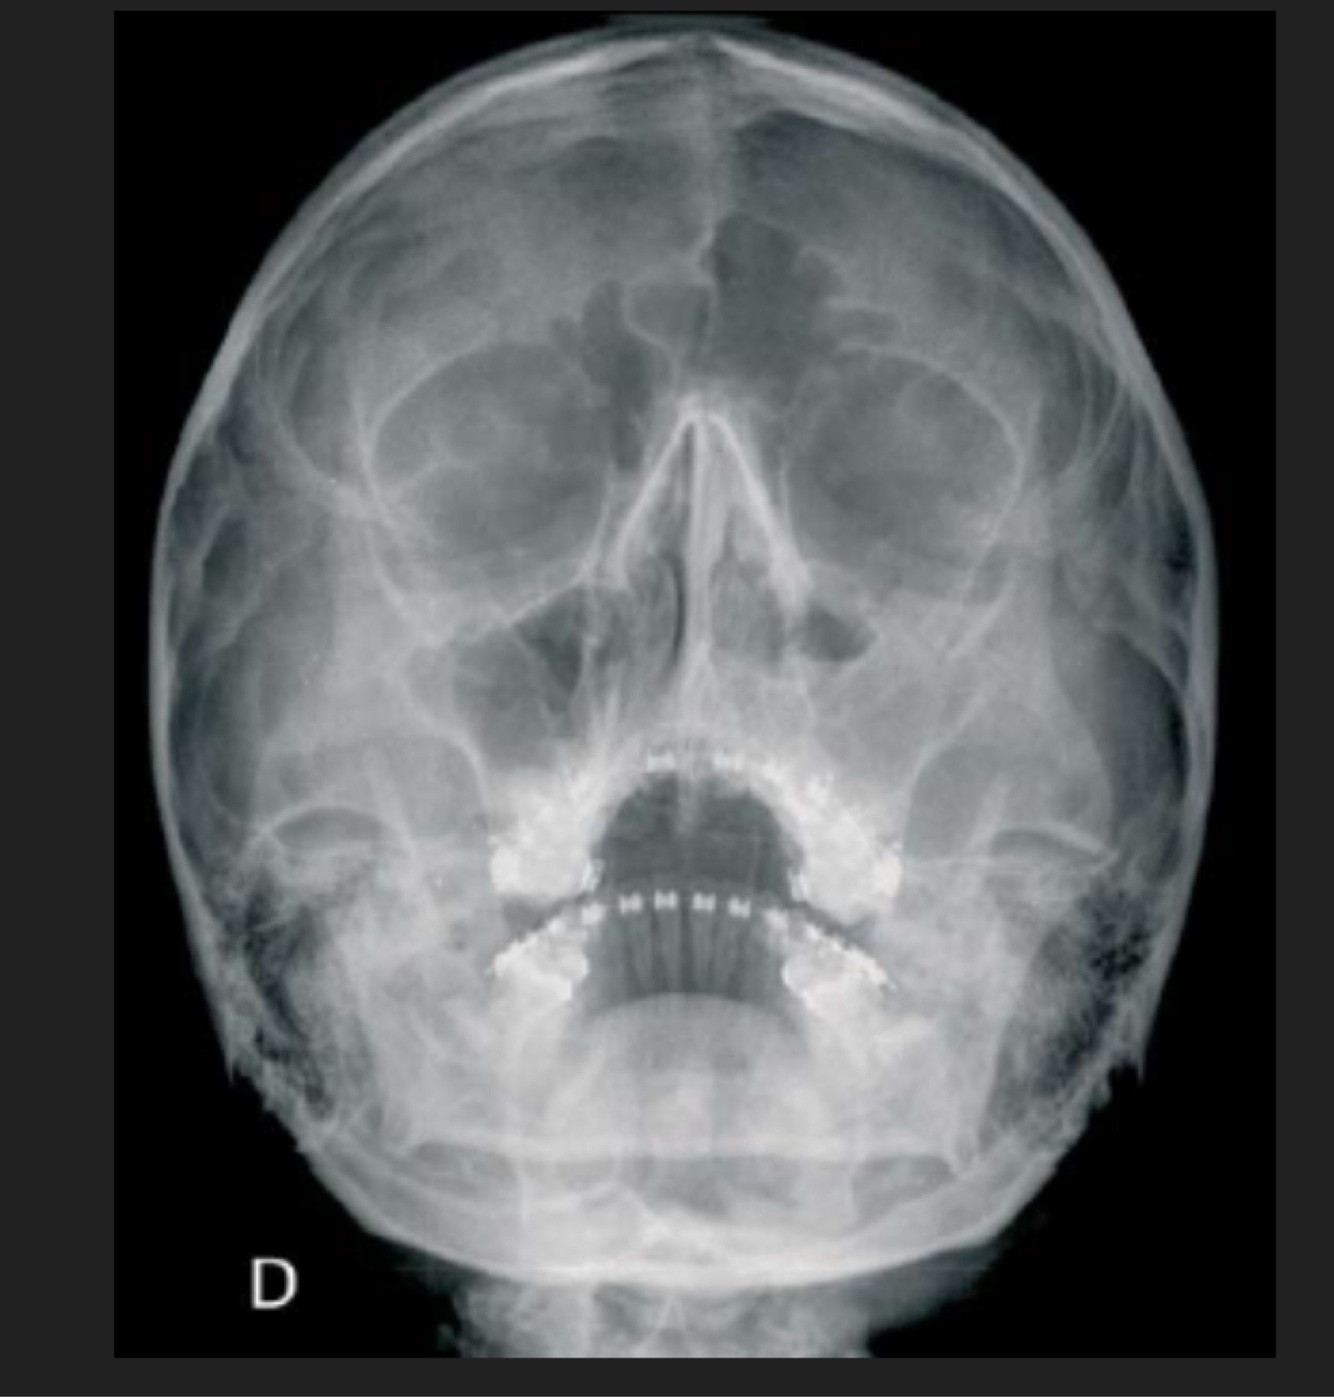

Q

Paciente con accidente automovilístico. Glasgow 5

A

Hemorragia subaracnoidea